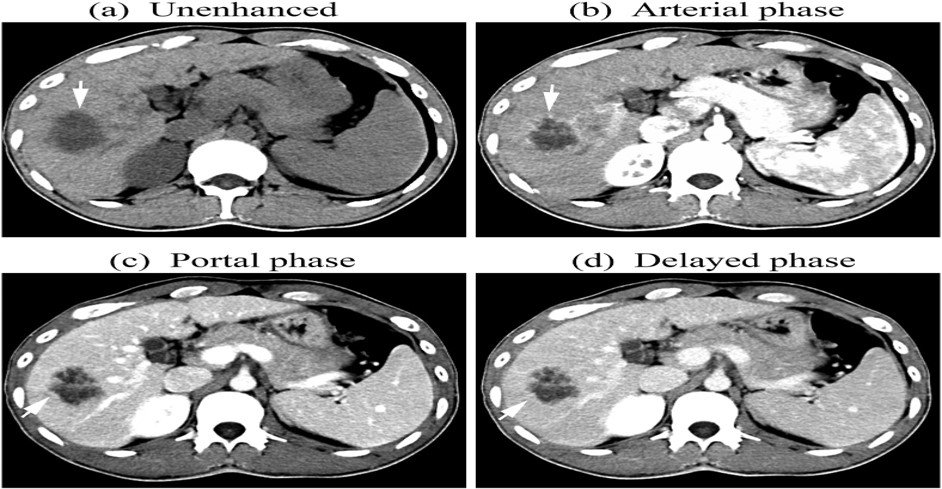

Focal Nodular Hyperplasia (FNH)

–Hyperplastic lesion, common in young females

–Intense homogeneous arterial enhancement

–Central scar characteristic

–Scar enhances on delayed phase

–MRI: T2 hyperintense scar

–No malignant potential

Summary of T1, and the various phases of the contrast study illustrating the nature of the focal liver lesion.

Note the enhancement of the central scar only on the delayed images when the rest of the lesion has washed out.

On the arterial phase, the lesion demonstrates intense homogenous enhancement, except for the central scar.